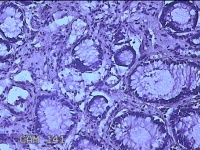

性别

男

年龄

40岁

临床诊断

混合痔

一般病史

反复肛门肿物突出15年。

标本名称

肛门肿物

大体所见

灰白暗红色肿物0.7x0.5x0.2cm一个,表面糜烂。

脱水、透明,浸蜡、脱蜡效果不佳,制片质量差。